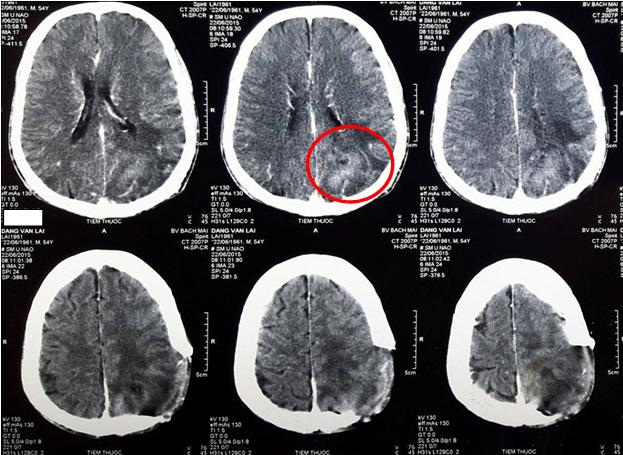

• Sau phẫu thuật lấy u não, bệnh nhân được chụp cộng hưởng từ sọ não đánh giá lại sau mổ, kết quả cho thấy vùng khuyết não vị trí đỉnh chẩm trái, còn tổ chức u ngấm thuốc và vùng phù não rộng xung quanh.

Hình 2: Hình ảnh còn tổ chức u sau mổ và vùng phù não xung quanh.( vòng tròn đỏ)